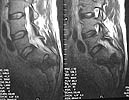

MR1

MR2